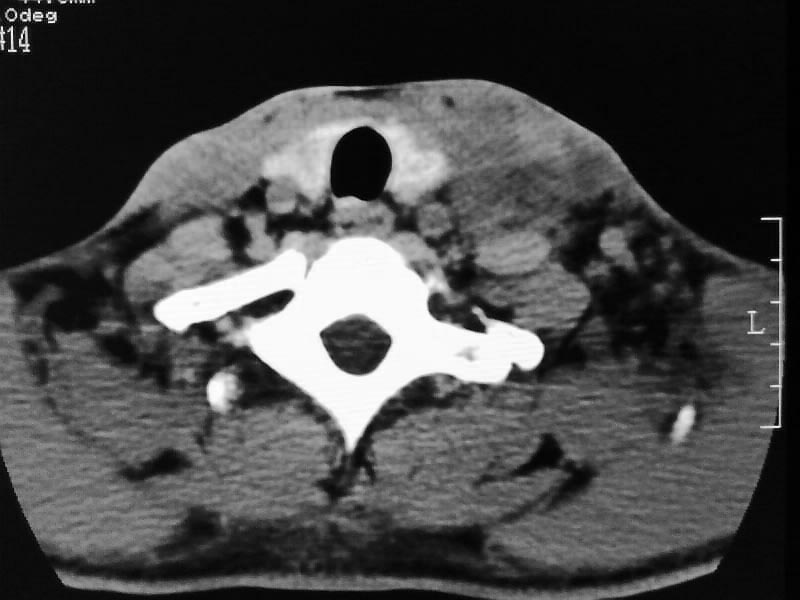

以下是引用余辉在2009-5-3 11:36:00的发言:[br]左侧胸锁乳突肌下方不规则肿物影,边界不清,内部密度不均,左侧颈外侧区脂肪增多,多发淋巴结肿大,考虑淋巴或神经来源肿瘤可能性大,不除外淋巴结炎,肌源性肿瘤及增生性肌炎等,活检